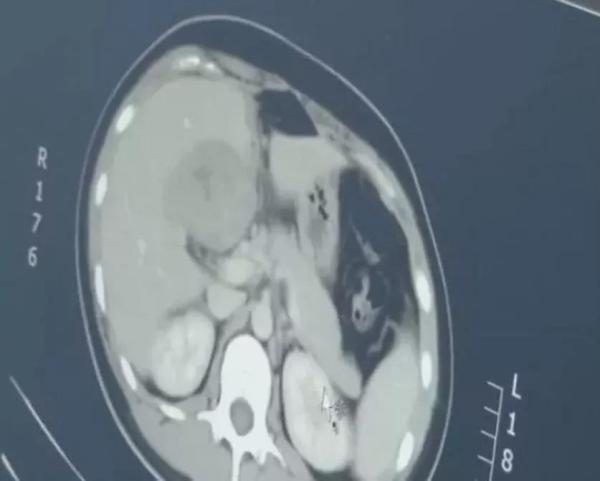

Hình ảnh màu xám bên trái là phôi thai, nằm gần gan.

Kết quả xét nghiệm máu cho thấy chị Long đã mang thai. Tuy nhiên, khi siêu âm, bác sĩ lại không tìm thấy bào thai nào trong tử cung nên yêu cầu chị Long đi chụp CT. Kết quả cho thấy có một khối lớn nằm ở gần gan và đó chính là bào thai.